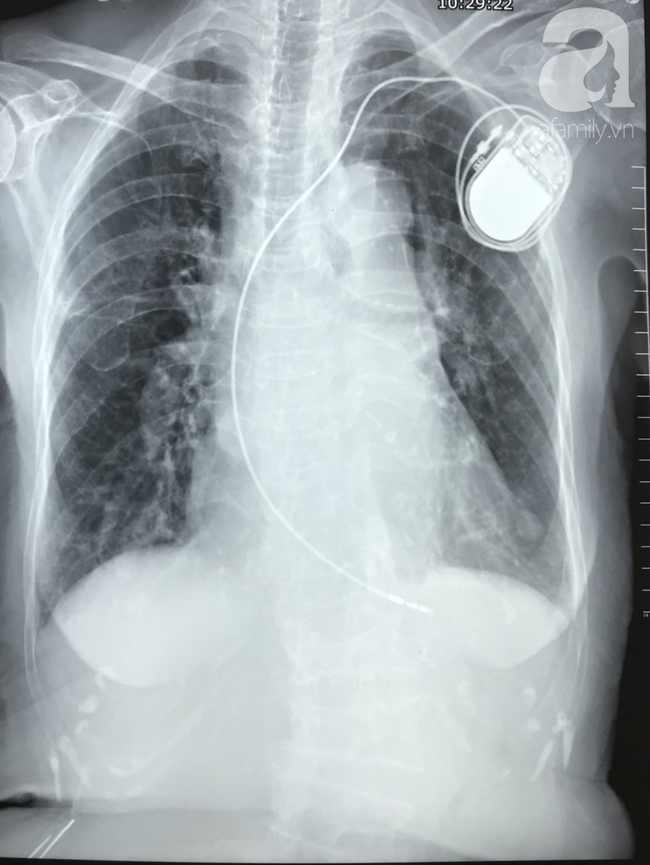

Bệnh nhân mắc bệnh không lây nhiễm nặng được điều trị tại BV Nhân dân Gia Định.